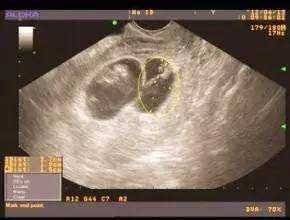

东吴B超监测法 诊断精确 安全无创

在所有测排卵的方法中,较为准确的就是B超监测法,苏州东吴中西医结合医院利用高分辨的实时超声已广泛应用于卵泡发育及排卵的形态学检查。超声监测的无创、可动态观察卵泡的发育是其优势。也是监测卵泡更直接的方法。在月经周期中,通过仪器可看到卵泡有小到大,由大到无。真真正正的眼见为实,准确无误。测排卵什么时候合适?点击咨询专家